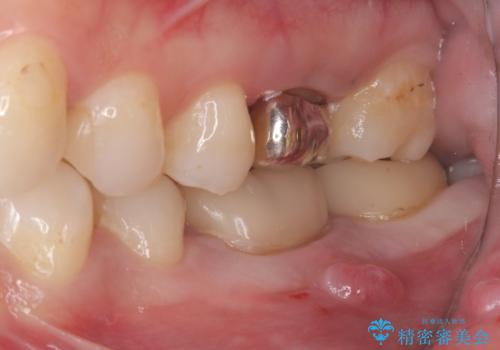

左下6番目の歯の周りに大きく透過像を認め、再根管治療後の予後が良くない可能性が大きく当院でも抜歯適用歯と説明しました。欠損部に対しインプラント治療や歯牙移植(左下の親知らずの移植)、ブリッジを提案し、歯牙移植を行うこととなりました。

保存が難しい左下6番目の歯を抜歯し、左下8番目の歯(親知らず)を抜歯窩に移植しました。歯牙移植後の動揺防止のため暫間固定を行っています。

また移植後2週間経過時点で根管処置が必要となります。